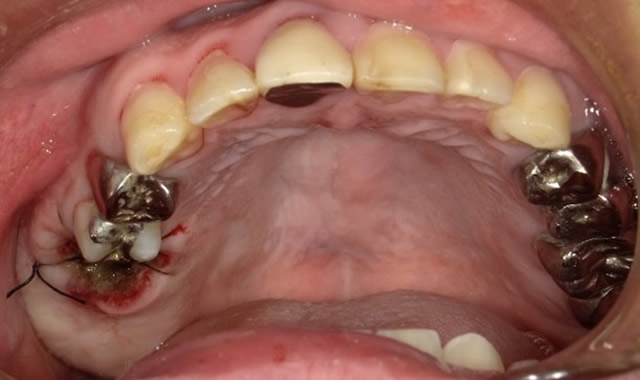

ケースⅡ:①上顎6番抜歯後に縫合

ケースⅡ:②止血床セット(内面に薬介在)